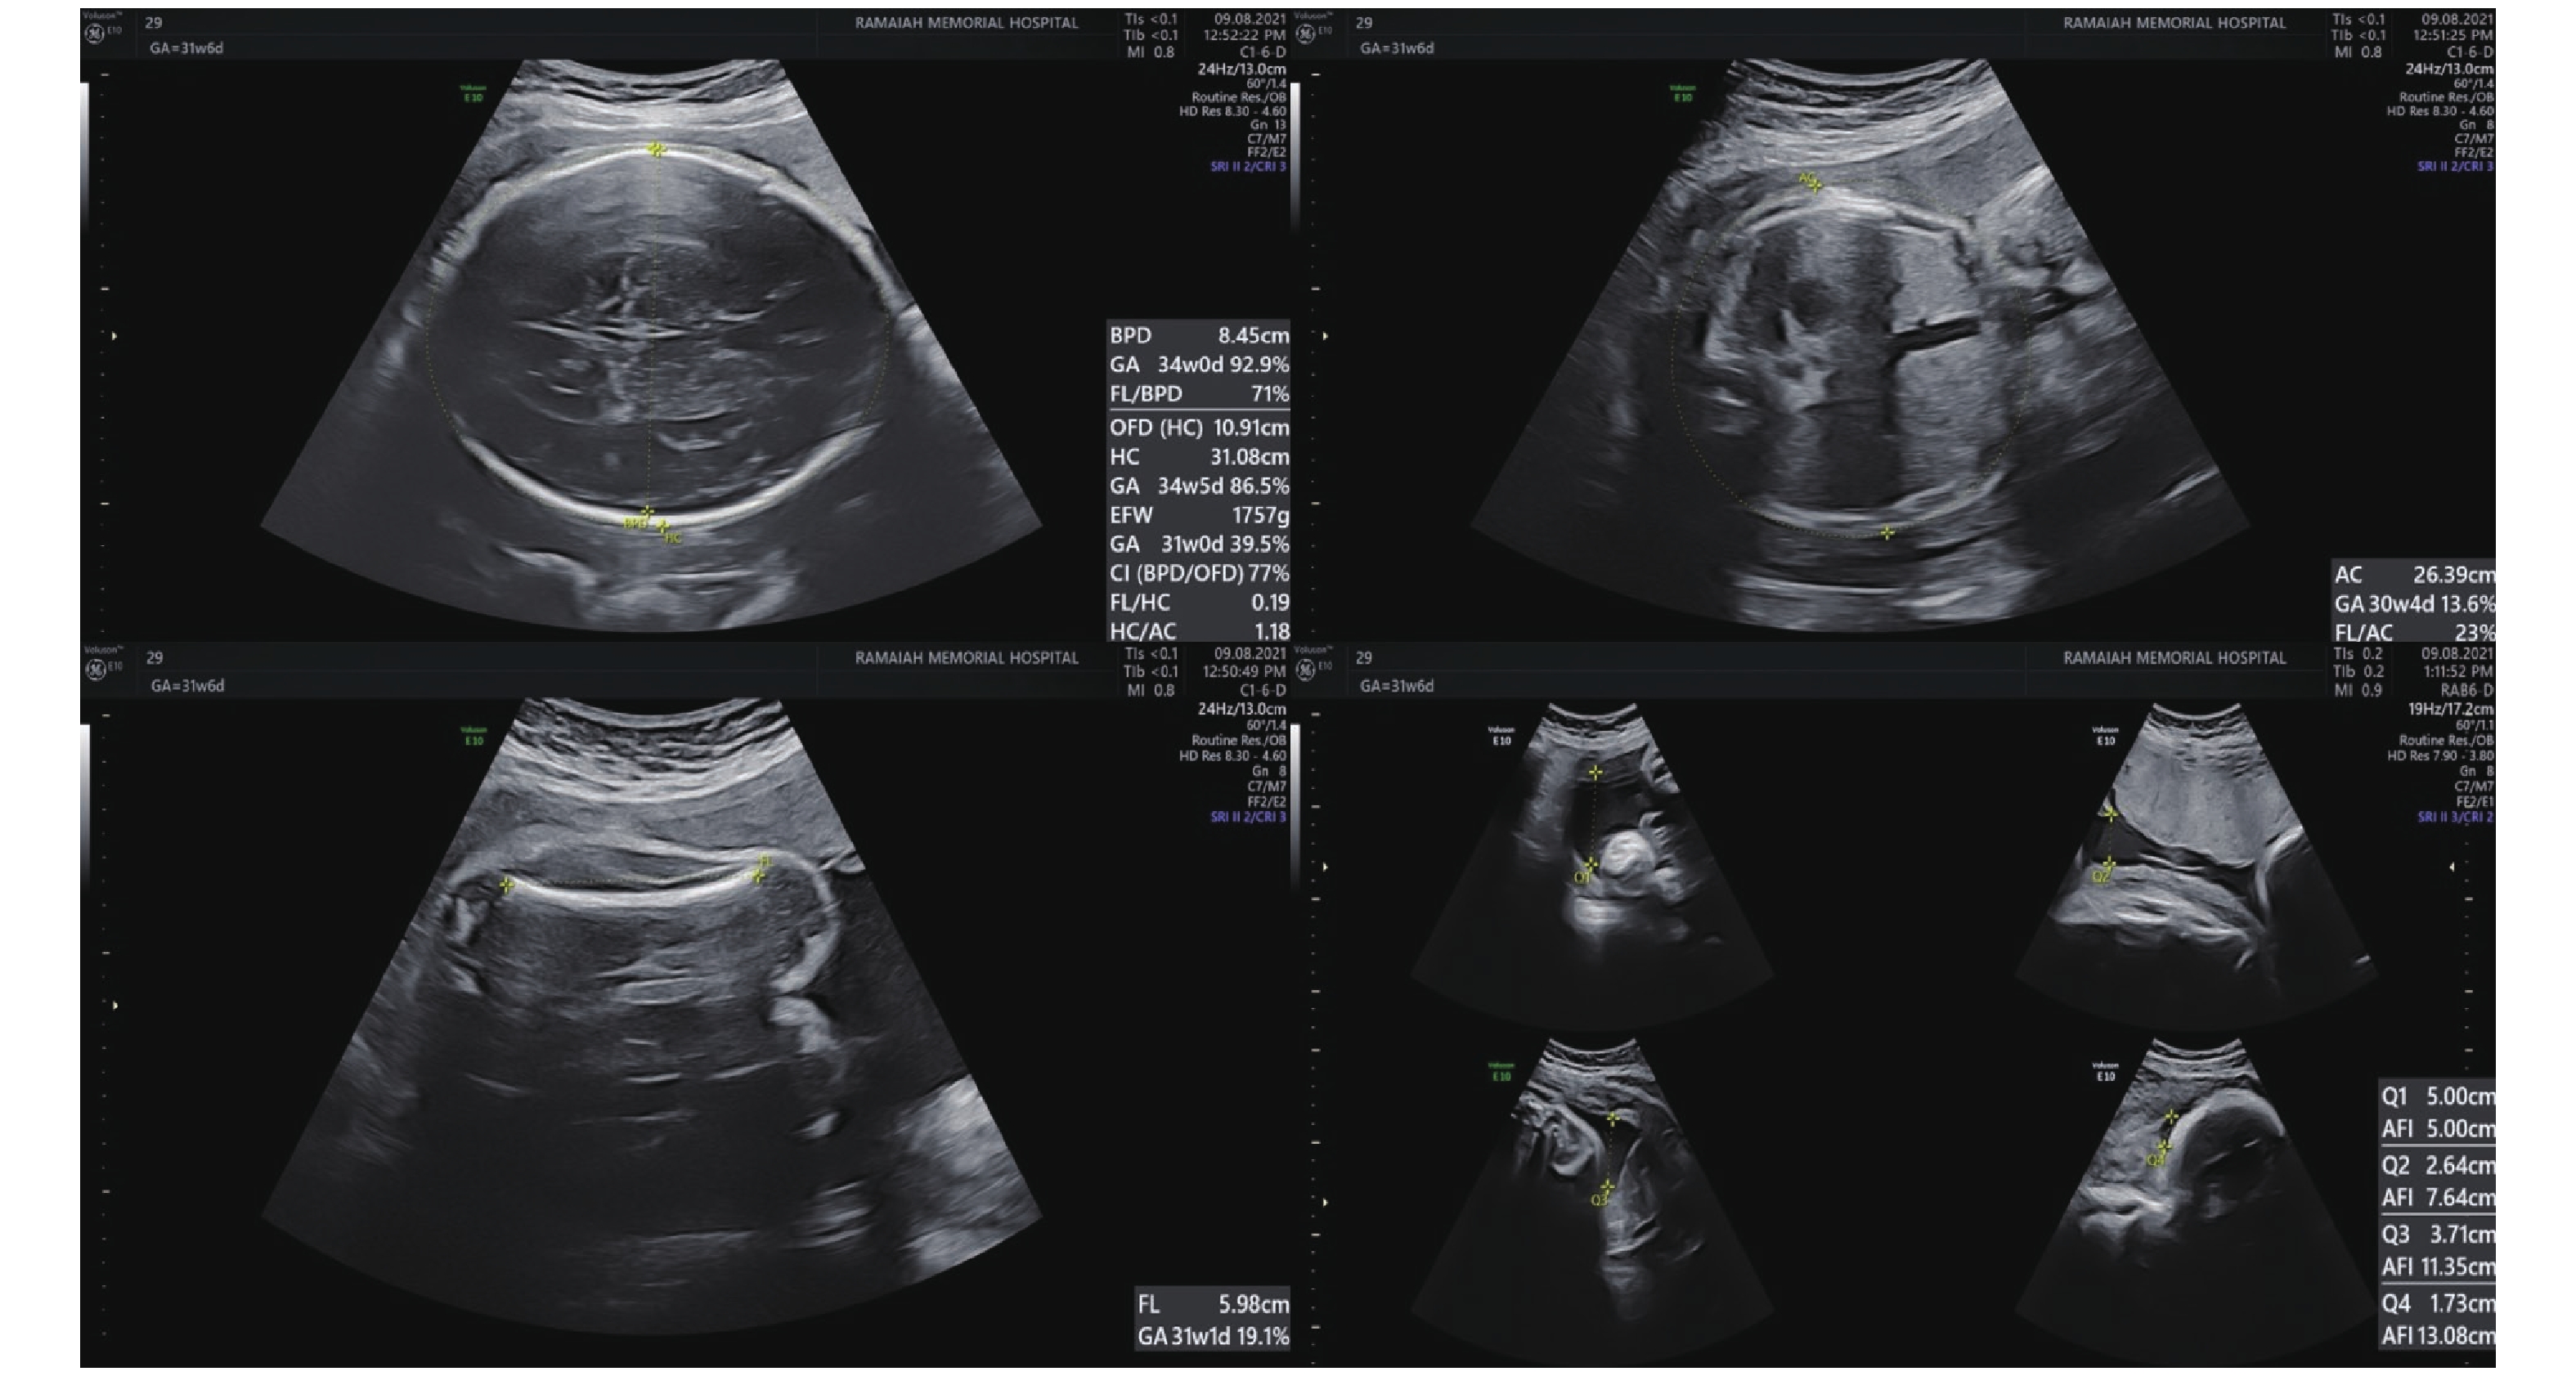

Figure 1

BPD, HC, AC, AFI and FL measured on 2D ultrasonography. BPD and HC measured on an axial plane that traverses the thalami and cavum septum pellucidum. AC is measured at the level of the fetal liver, where the umbilical vein joins the portal vein, and includes the stomach and spine. BPD, biparietal diameter; HC, head circumference; AC, abdominal circumference; FL, femur length. (Images were acquired on E10 Voluson ultrasound machine)"